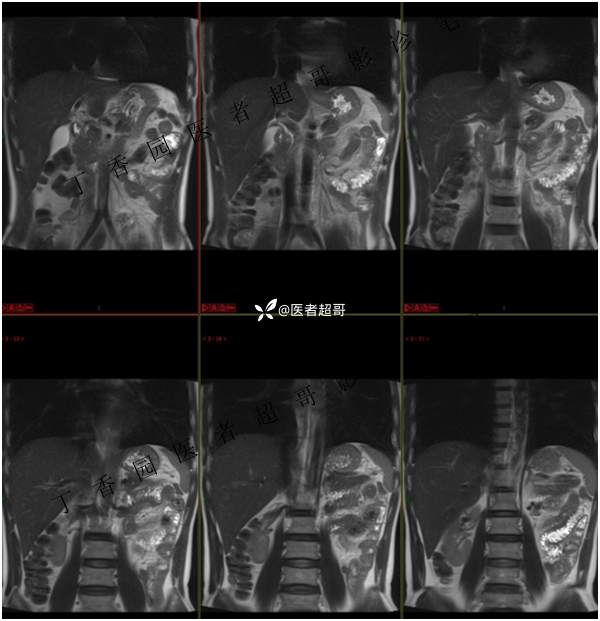

肝胃间隙肿瘤,间质瘤?平滑肌瘤?还是鞘瘤?有结果,请分析!

现病史:患者于3天前查体行肝胆脾胰肾彩超示肝内实性占位,无恶心、呕吐,无发热、寒战,无腹胀、腹泻,进一步于医院行上腹部CT增强示:肝胃交界处肿块。未行特殊治疗。今患者为求进一步治疗,来我院就诊,门诊以“肝占位性病变”收入院。患者自发病以来,神志清,精神可,饮食睡眠可,二便可,体重近期未见明显变化。